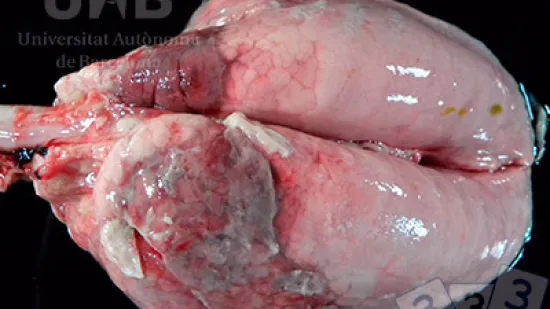

Semaine du 03-Mai-2021

Sur cette photo, on observe une atrophie thymique sévère sur un porcelet; de fait il y a un reliquat dans la zone péricardiaque, autour de la cavité thoracique. Lequel de ces agents infectieux peut avoir provoqué cette lésion ?